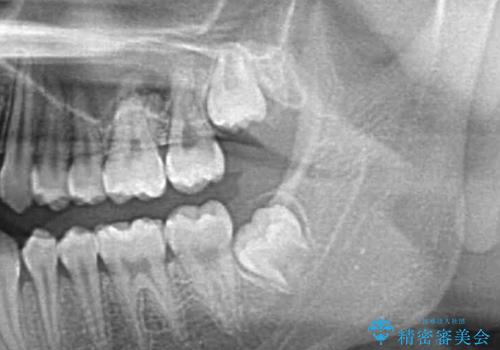

- 親知らずの抜歯希望で来院されました。

左側の親知らずを上下同時に抜いていきます。

時間は約60分で施術しました。

親知らずは入院せずとも通院で片側上下同時に抜くことが可能です。

手前の歯の虫歯リスクを下げるためにも、骨から出てきた親知らずは抜くことをお勧めします。